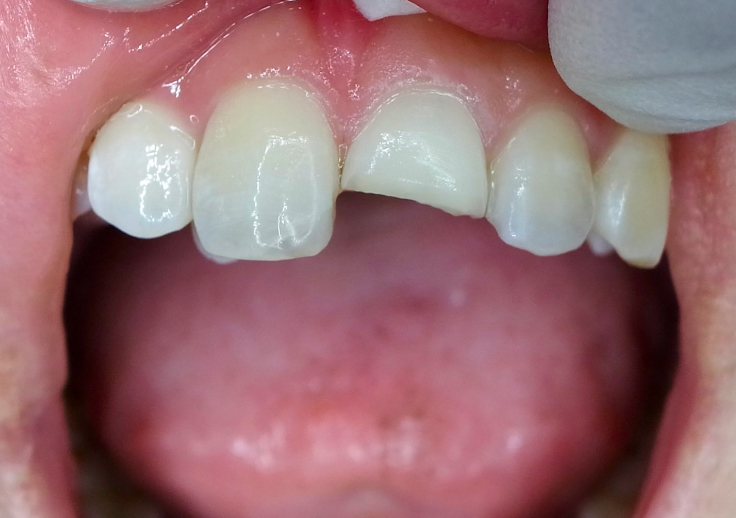

食事中に硬いものを噛んだ拍子に、歯が欠けたり折れてしまうことがあります。

ただし、おせんべいやナッツなど一般的な硬さの食べ物で、健康な歯が簡単に折れることはほとんどありません。

歯が折れたり欠けたりした場合、

・むし歯が進行していた

・詰め物や被せ物の下でトラブルが起きていた

・歯に目に見えない細かなヒビが入っていた

など、何らかの異常が起きていた可能性が高いと考えられます。

また、スポーツ中の事故や転倒による破損も、

「痛みがないから大丈夫」と放置するのは危険です。

見た目に小さな欠けでも、内部でダメージが広がっていることがあります。

歯は、一度折れたり欠けたりすると自然に元に戻ることはありません。